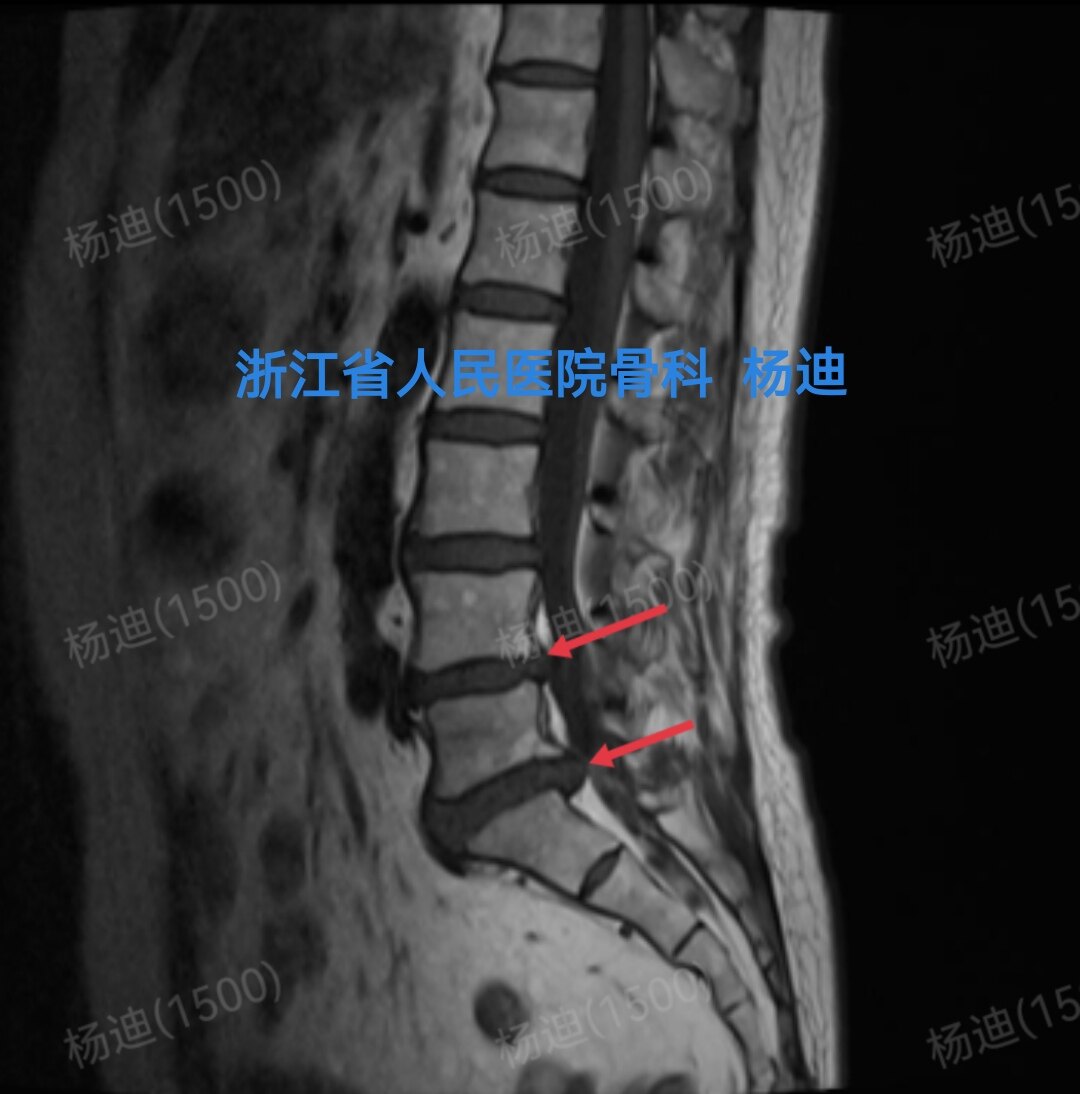

图为腰椎磁共振T2相检查结果,提示腰4/5、腰5/骶1椎间盘突出(红色箭头),硬膜囊受压。

图为腰椎磁共振T2相检查结果,提示腰4/5、腰5/骶1椎间盘突出(红色箭头),硬膜囊受压。

图为腰椎磁共振T1相检查结果,提示腰4/5、腰5/骶1椎间盘突出(红色箭头),硬膜囊受压。

图为腰椎磁共振T1相检查结果,提示腰4/5、腰5/骶1椎间盘突出(红色箭头),硬膜囊受压。